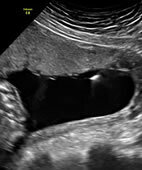

Eine spezielle Punktion bei Schwangeren ist die Fruchtwasserpunktion

© W&B/Ulrike Möhle/Szczesny

Fruchtwasserpunktion unter Ultraschallkontrolle: Die Fruchtblase ist dunkel, die Spitze der Punktionsnadel als heller Reflex sichtbar

© W&B/Privat